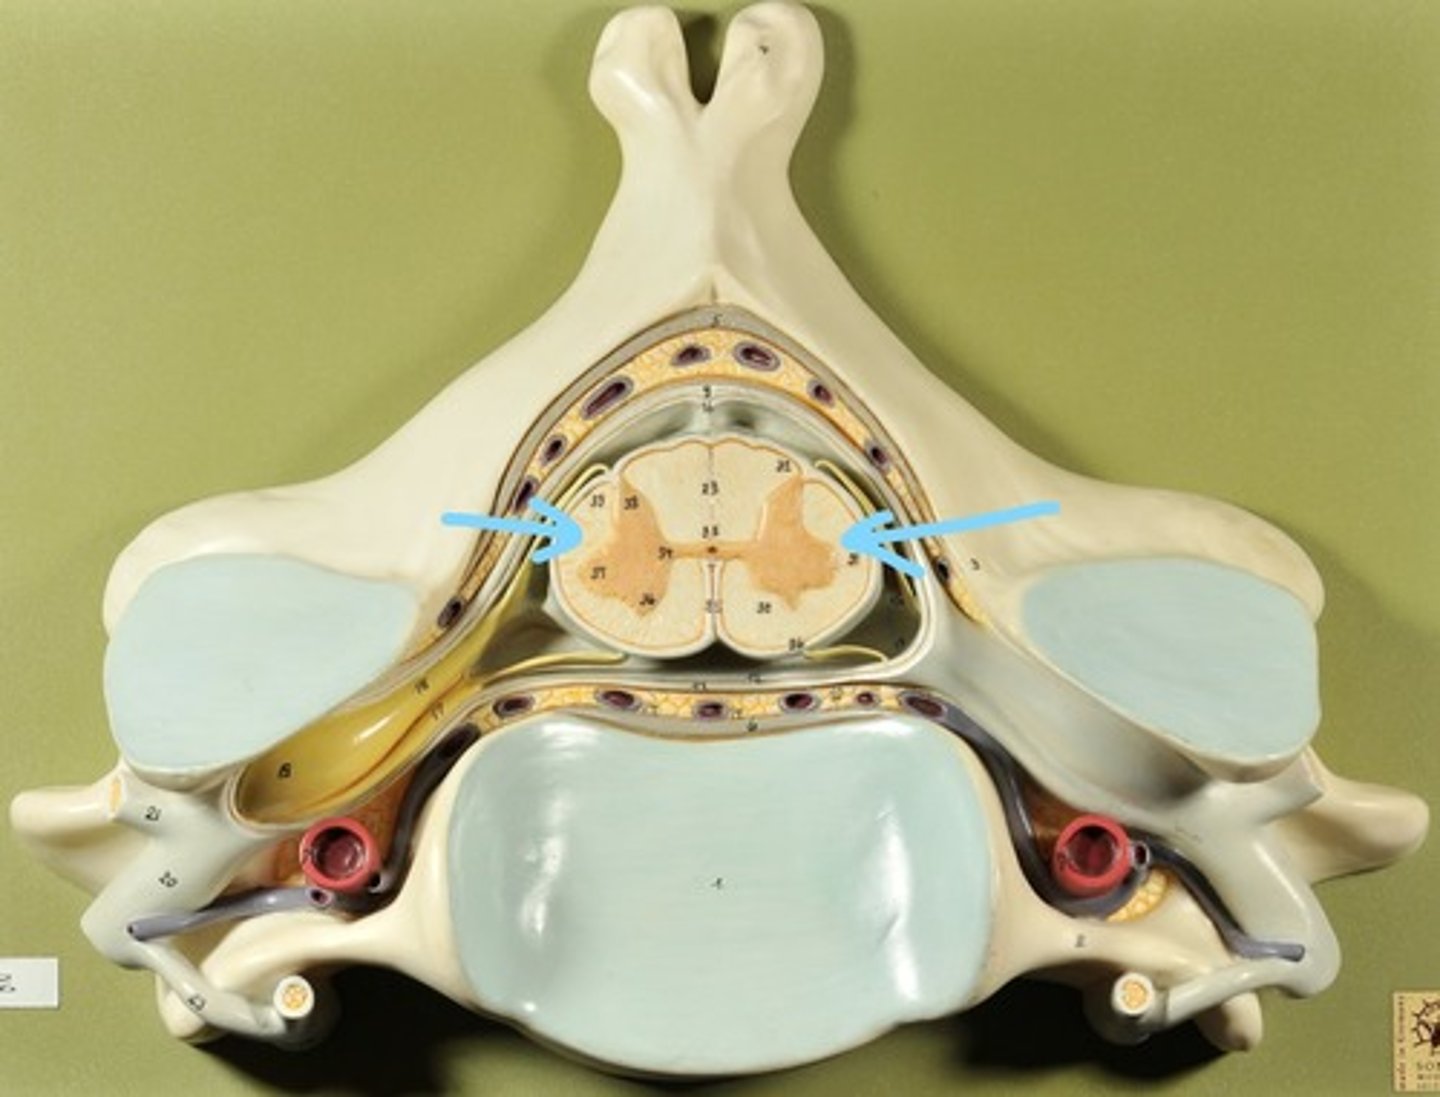

Identify all structures of spinal cord

White Matter of spinal cord

gray matter of spinal cord

Ventral Horns (gray matter)

Lateral Horns (gray matter)

Dorsal horns (gray matter)

Anterior Columns (white matter)

Lateral Columns (white matter)

Posterior Column (white matter)

central canal of spinal cord

Identify all structures

Pia Mater

Subarachnoid Space

Arachnoid mater

Subdural Space (brown line)

Dura mater

Epidural Space

Dorsal Root Ganglion

Dorsal Root

Ventral Root

Spinal Nerve